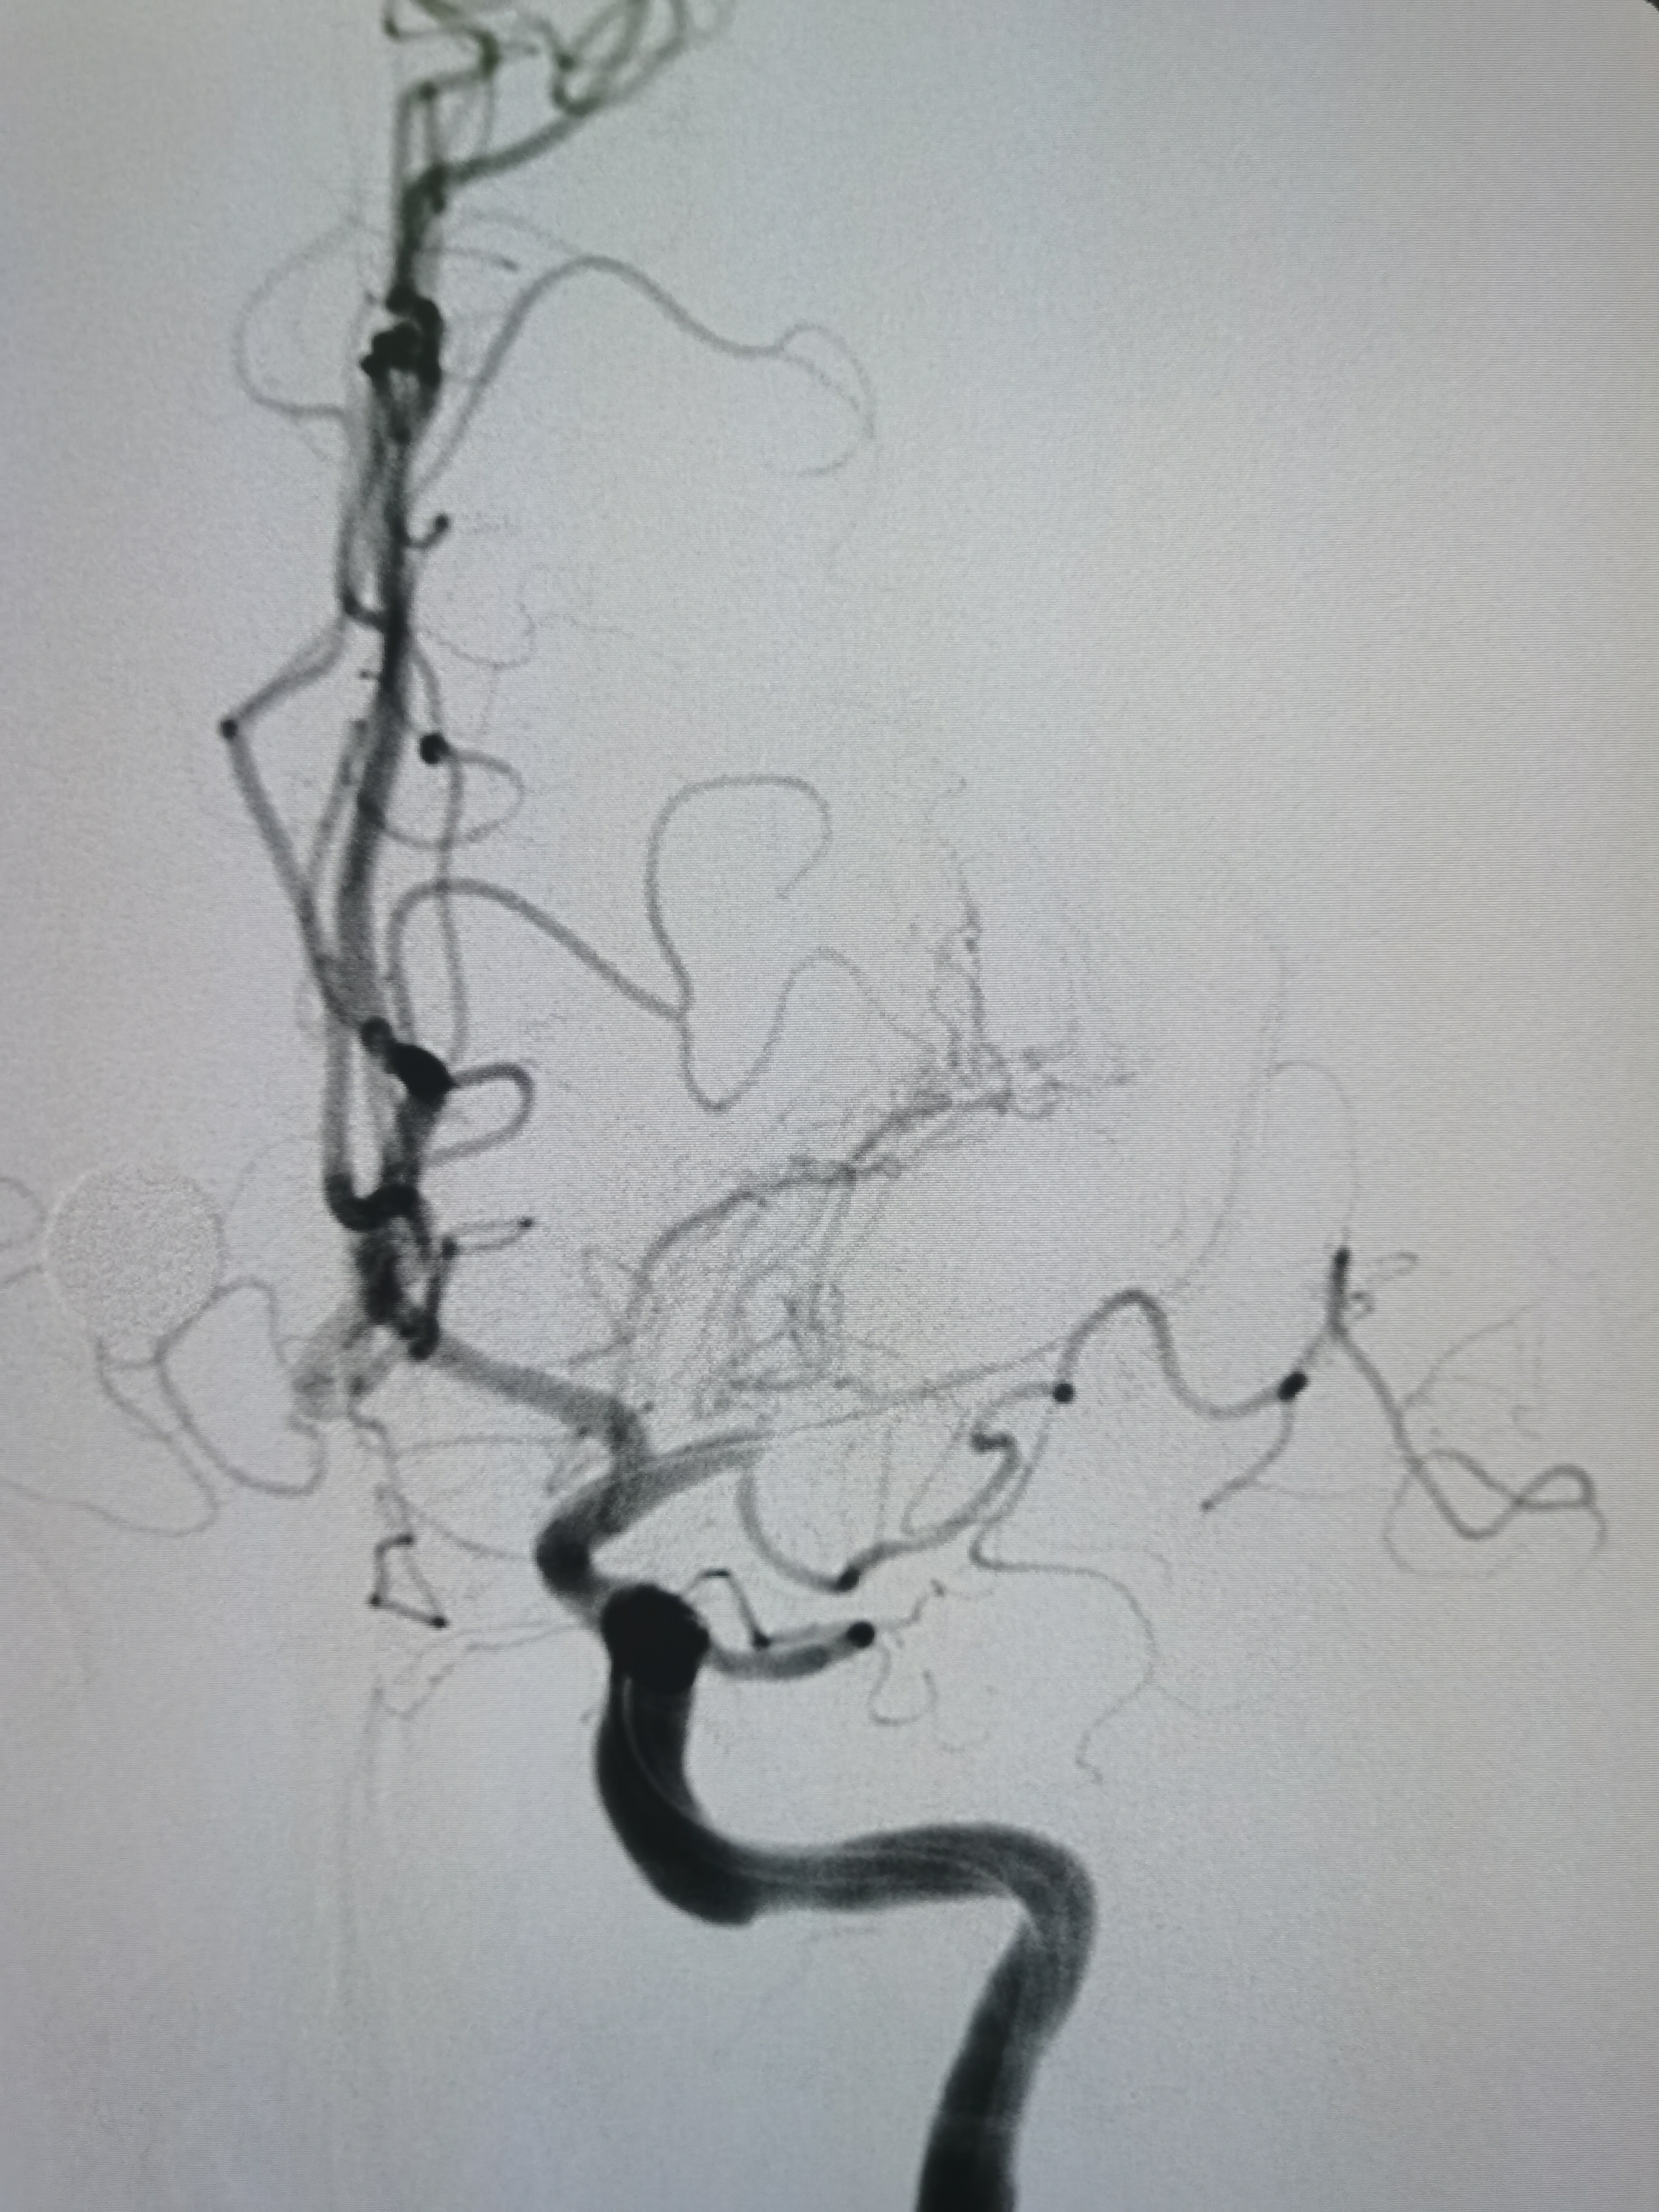

侧位见左侧大脑中动脉闭塞。

晚期可见左侧大脑中动脉返流。

正位见左侧大脑中动脉闭塞。

动脉晚期可见左侧大脑中动脉M2段返流。

扩张后造影见血管再通,血流通畅。

侧位造影见血流通畅。

观察15分钟后造影血流通畅,未见夹层及明显弹性回缩。

术前术后对比